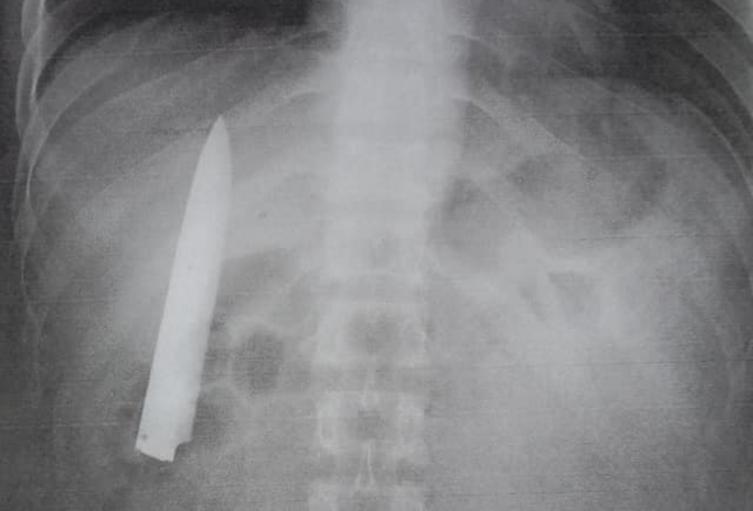

¡Increíble! Hombre apuñalado pasó 14 meses con la hoja del cuchillo en su torso

Un hombre sobrevivió catorce meses con una hoja de cuchillo dentro de su torso. El insólito caso se presentó en la ciudad de Kidapawan, Filipinas.

Kent Ryan Tomao fue víctima en enero de 2020 de una brutal agresión por parte de unos adolescentes que lo apuñalaron. El personal médico que lo atendió en aquella ocasión, en una evidente irresponsabilidad, no le realizó exámenes para verificar la profundidad de la herida, sino que procedió a suturarla.

Hace unos días, Tomao aplicó a un empleo en ese país, por lo que le solicitaron unos requisitos en los que incluía una prueba de rayos X. De esta forma, el hombre se dio cuenta que llevaba catorce meses con la hoja de un cuchillo en el interior de su cuerpo.

Al ser preguntado por medios locales, como ABS-CBN, si nunca notó la presencia de un objeto extraño en su torso, Tomao aseguró que cuando el clima era frio sentía algo de dolor en el pecho, pero no le prestaba atención.

Asimismo, explicó que el cuchillo debe ser extraído lo más pronto posible, ya que se encuentra muy cerca de los pulmones y corre riesgo su vida.